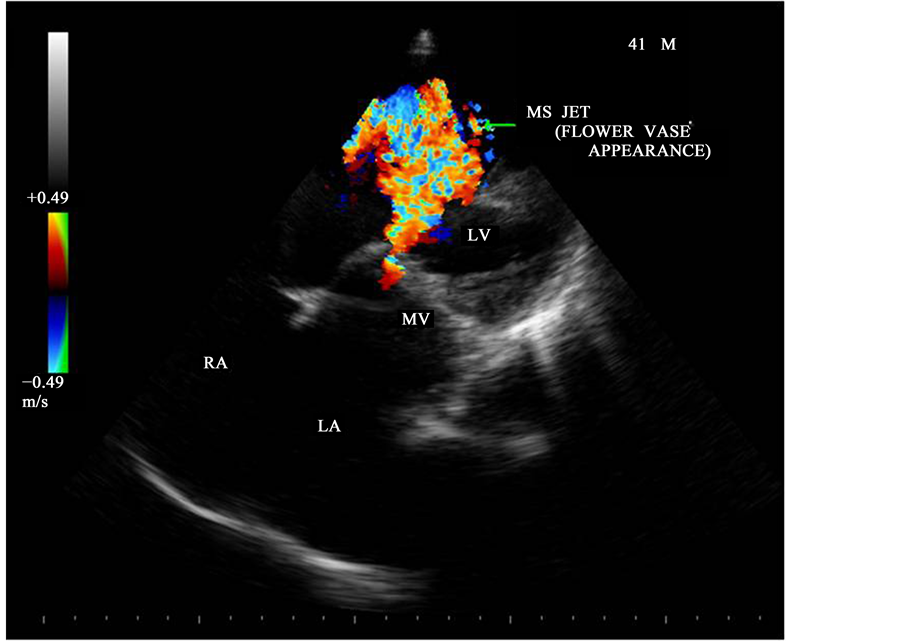

Figure 24. Apical four chamber view-showing the MS jet―“flower vase appearance”.

Acute insult of rheumatic fever on mitral valve leads to the formation of multiple inflammatory foci consists of Aschoff bodies, perivascular mononuclear infiltrate in the endocardium and myocardium. With time, the valve apparatus become thickened, calcified and contracted. Commissural adhesion occurs as shown in Figure 18 and ultimately resulting in mitral stenosis after a long latent period of streptococcal infection due to autoimmune mediated inflammation. Due to commissural fusion, the leaflets open with a “doming” motion as shown in Figure 9 and it results in reduction of the orifice and the conversion of the mitral leaflet-chordal apparatus from a tubular channel to a “funnel-shaped” orifice. The substantial fibrosis and calcification at the orifice of mitral valve limits inflow from left atrium to left ventricle and this limiting orifice is planimetered at the valve tips in mid-diastole as shown in Figure 20 and Figure 21, the orifice area correlate well with hemodynamic data and anatomic valve area [54] .

In general, rheumatic mitral stenosis results in a central stenotic orifice with flow directed from the center of the left atrium towards the apex of the left ventricle and collide with AR jet, producing a “bow and arrow” appearance as shown in Figure 27 and Figure 28. The differential features of etiological aspects of mitral stenosis (MS) are shown in Table 1.